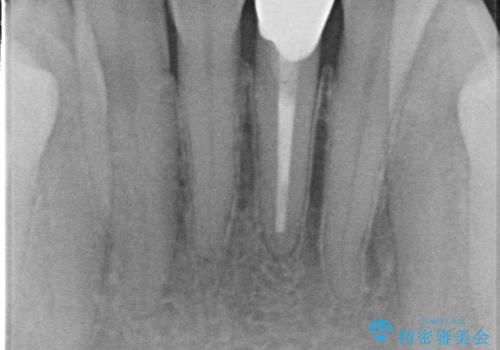

- 下顎前歯が茶色いのが気になるのでセラミックで治療したいといらっしゃった方の症例です。

再根管治療後、オールセラミッククラウン(スペシャル)による補綴を行いました。